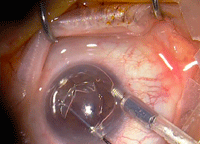

Figura 4. En el ojo receptor se debe desgarrar la Descemet (descemetorrhexis). La mejor visualización se obtiene mediante el relleno de la CA con burbuja de aire.